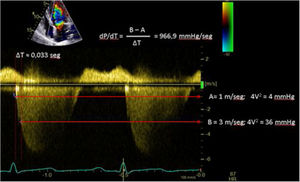

| C.2.1. dP/dt. La derivada de la presión ventricular respecto al tiempo (dP/dt) es un parámetro más frecuentemente utilizado durante el cateterismo cardiaco del ventrículo izquierdo.Por ecocardiografía, aunque no podemos medirlo, en presencia de insuficiencia mitral podemos estimar la derivada de la velocidad de su curva (dV/dt). No debe ser usado en casos de insuficiencia mitral aguda, estenosis aórtica significativa o hipertensión arterial o asincronía evidente, donde valores descendidos no implican disfunción miocárdica. | ||

Uno de los cuadros clínicos más difíciles de manejar en el PC es la insuficiencia mitral que se produce por un movimiento anómalo de la valva anterior (SAM), generando un gradiente de presión en el TSVI o mesoventricular, arrastrando y succionando la valva anterior mitral (fig. 3). Debe sospecharse en casos con hipertrofia concéntrica, miectomía o implante de prótesis mitral con postes grandes que se dirigen hacia el TSVI, estados de hipovolemia y/o necesidad de soporte vasoactivo ascendente sin respuesta tensional apropiada.

PC de bypass coronario en paciente con hipertrofia del VI concéntrica: obstrucción dinámica TSVI por exceso de soporte inotrópico e hipovolemia postoperatoria, generando insuficiencia mitral severa por movimiento septal anterior (SAM). Obsérvese el flujo de aceleración progresiva por Doppler continuo.

Video 1. Gradiente dinámico en el POI tras revascularización coronaria en paciente con hipertrofia ventricular izquierda concéntrica previa.